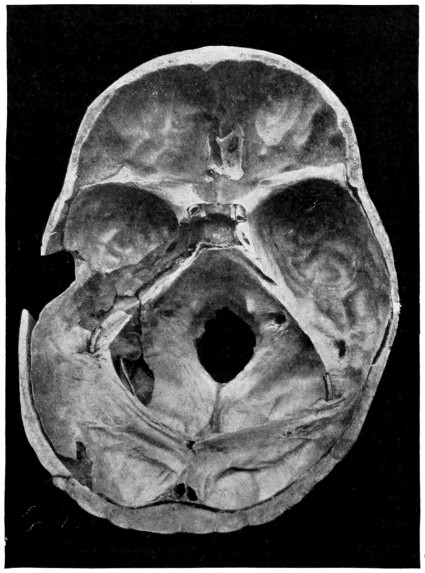

50 A and B. The inner aspect of the skull and the same seen on transillumination 137

51. To illustrate compression of the brain as produced by an extra-dural hæmorrhage from the middle meningeal artery[x] 141

52 A and B. The operative treatment of middle meningeal hæmorrhage 144, 145